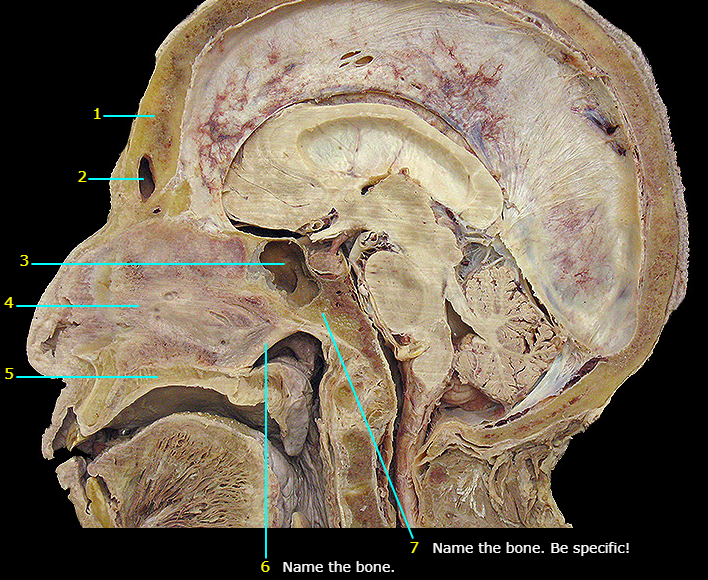

Name #2

Perpendicular plate of ethmoid

Name #3

Septal cartilage

Name #1

Vomer (#4)

Sphenoid

Sphenoid sinus

Lateral plate of pterygoid

Medial plate of pterygoid

Hard palate

Maxilla

Name the bone

Mandible

Epiglottis (epiglottic cartilage)

Name the bottom structure

Thyroid cartilage